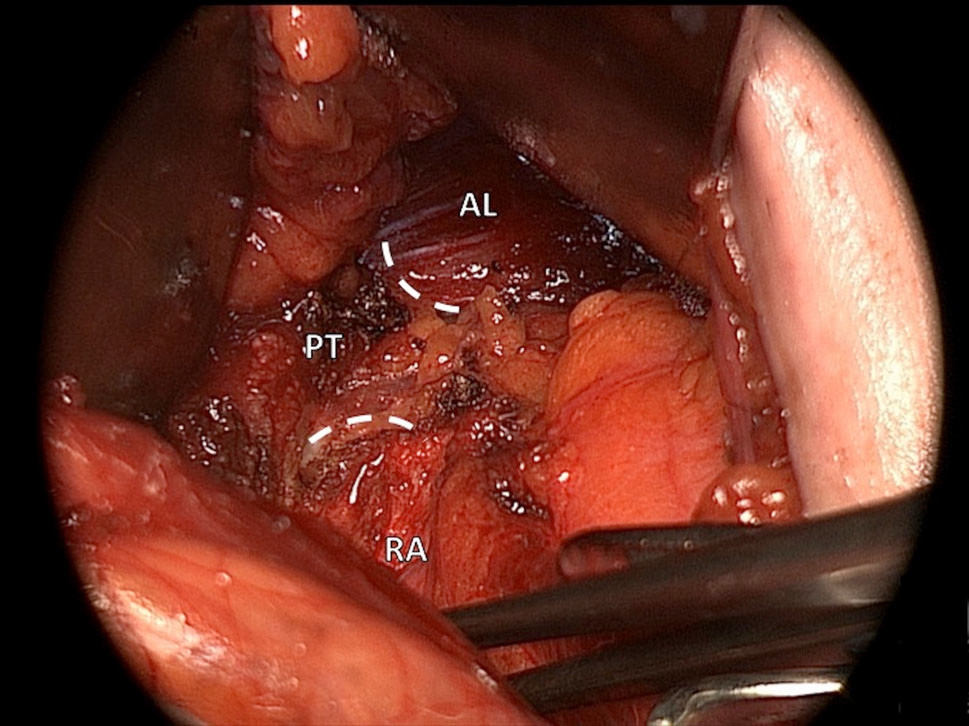

La ténotomie divise le vecteur de force vertical (aponévrose commune) qui intègre le tendon de l’adductor longus et la gaine du rectus abdominis afin de dissiper les contraintes au niveau de l’os pubien (figure 5).

La ténotomie est réalisée à 1-2cm du tubercule pubien et s’étend inférieurement et médialement, la manœuvre vise à séparer le tendon du muscle adductor longus des fascias le recouvrant.

Figure 5 : Ténotomie de l’adductor longus (AL) et du rectus abdominis (RA).